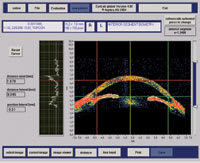

Stratus OCT: RNFL scan. |

The Stratus OCT (Carl Zeiss Meditec), used clinically for the evaluation of the retina, employs a 0.8 nm wavelength that cannot penetrate the sclera. As such, it is not ideal for assessing the anterior segment. However, the anterior segment version, the SL OCT, uses a longer wavelength that produces clinically useful results. Preliminary clinical studies suggest that anterior segment OCT compares favorably with conventional gonioscopy in its ability to identify potentially occludable angles.